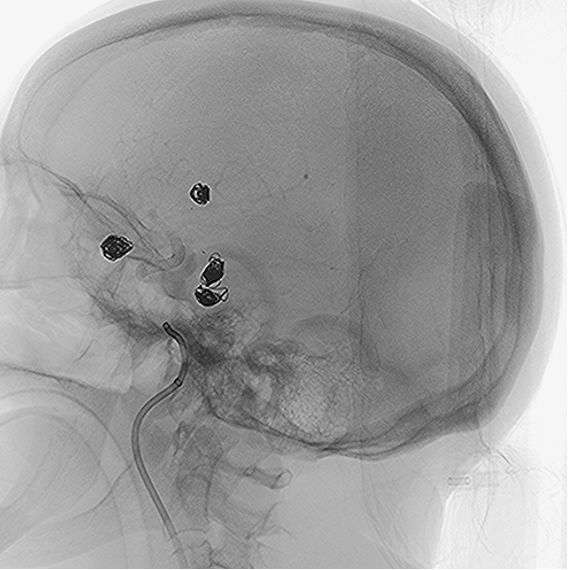

• The patient presented with multiple unruptured giant wide-neck aneurysms. A pre-treatment panangiography revealed a right posterior communicating artery aneurysm measuring approximately 8x8mm and an additional 8x6mm saccular aneurysm in the left azygos pericallosal artery—an exceedingly rare anatomical variation.

• The left middle cerebral artery aneurysm (9x5mm) had previously been treated with a coil but required further intervention.

• Under general anesthesia, a puncture was performed on the right femoral artery, and a CEREBASE 8F introducer catheter was inserted.

• The left internal carotid artery (ICA) was accessed and a pathway was built using TJWY’s FREPASS microcatheter.

• A 5x20mm NUVA flow diverter, designed by TJWY, was deployed to treat the aneurysm in the posterior communicating artery with precision, achieving immediate blood flow stagnation.

• The neck of another aneurysm in the pericallosal artery was protected with a 10mm PCONUS intrasaccular device, and successfully embolized with 3 coils.

• The NUVA flow diverter demonstrated excellent wall apposition without complications.

• Post-surgery, branch vessels were fully preserved, and the patient’s recovery was smooth with no adverse events.